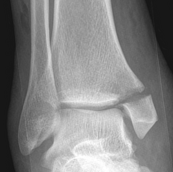

Osteoarthritis

Swierstra et al EFORT Open Rev 2022

- systematic review

- overall incidence of post-traumatic OA 25%

Beak et al Foot Ankle Int 2022

- risk factors for OA in 330 patients

- increased risk with fracture dislocations / posterior malleolar fractures / malreduction

Ankle OA Post ORIF